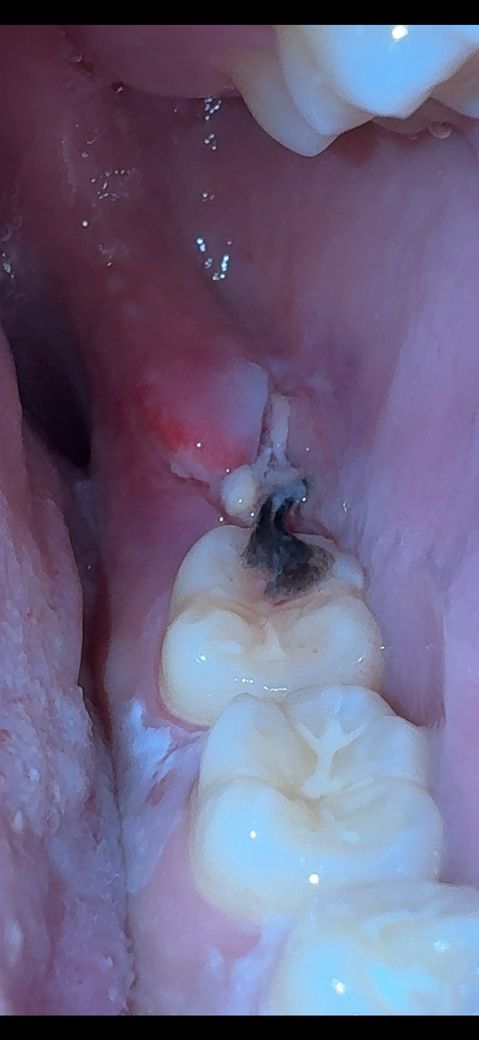

3.사진에 보시면 염증이나 무슨 이상이 있나요? 실밥옆에 노란 고름(?)같은게 뭔지 궁금합니다

• 1번 째 사진

-> 치유과정에서 생기는 염증,육아조직이 음식물 등 이물질과 섞여있는것 같습니다